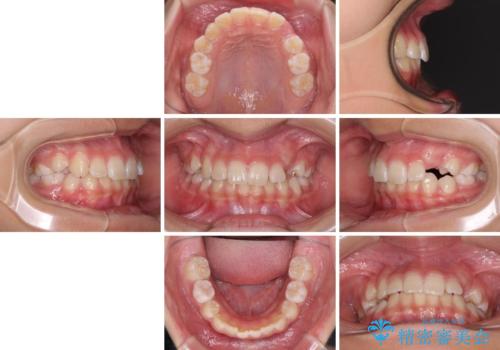

- 小学校での定期歯科検診にて歯列不正を指摘されたとのことで来院された患者様です。

左上の犬歯が低位に埋伏しており、将来八重歯になるリスクが高いと判断されたため、補助装置とワイヤーを用いて犬歯を通常の位置まで移動させることとしました。